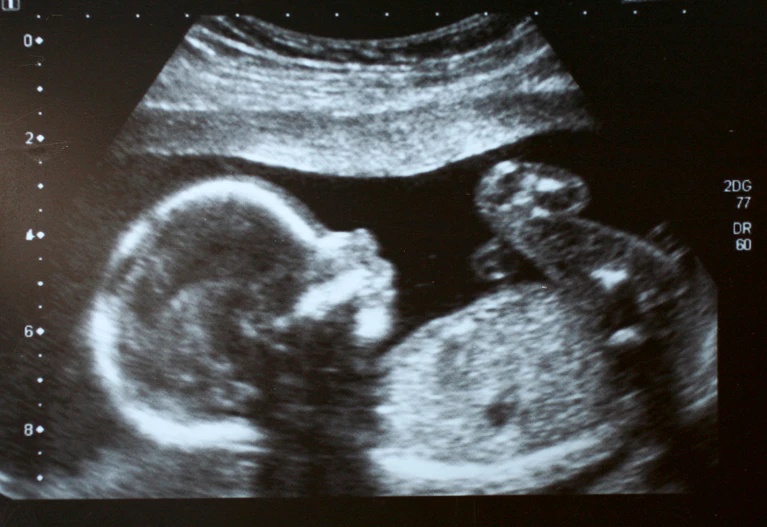

患有严重脊髓性肌萎缩症的婴儿缺乏足够的蛋白质来维持运动神经元。图片来源:YsaL/Getty